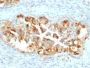

Mesothelin is a 40 kDa glycosyl-phosphatidylinositol-anchored glycoprotein cleaved from a 69 kDa precursor protein. Mesothelin immunoreactivity is high in cancers of the ovary (serous papillary, endometrioid and undifferentiated) and pancreas, with less frequent staining seen in adenocarcinomas of the endometrium, lung and stomach/esophagus. Mesothelin is one of the most sensitive markers for mesothelioma.Primary antibodies are available purified, or with a selection of fluorescent CF® Dyes and other labels. CF® Dyes offer exceptional brightness and photostability. Note: Conjugates of blue fluorescent dyes like CF®405S and CF®405M are not recommended for detecting low abundance targets, because blue dyes have lower fluorescence and can give higher non-specific background than other dye colors.

Positive Control

CAPAN-2 or HeLa cells. Lung Mesothelioma.

Mesothelioma|Ovarian cancer|Pancreatic cancer

IHC (FFPE) (verified)

Higher concentration may be required for direct detection using primary antibody conjugates than for indirect detection with secondary antibody|Immunohistology (formalin): 1-2 ug/mL for 30 minutes at RT|Staining of formalin-fixed tissues requires boiling tissue sections in 10 mM citrate buffer, pH 6.0, for 10-20 minutes followed by cooling at RT for 20 minutes|Optimal dilution for a specific application should be determined by user